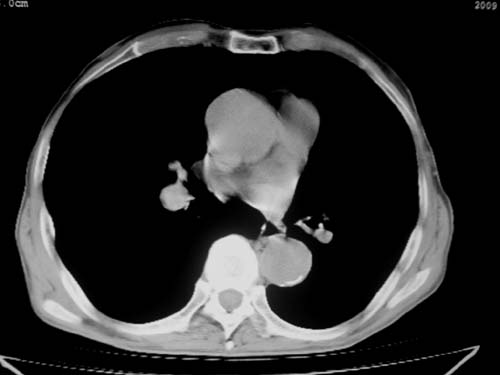

标题: CT19736:男,76岁,咳嗽,胸痛 [打印本页]

标题: CT19736:男,76岁,咳嗽,胸痛

支持左上肺周围型肺癌性并空洞形成伴胸椎转移。

支持 左上肺周围型肺癌性并癌性空洞形成伴胸椎转移。

考虑癌性空洞并胸椎转移。

左上肺癌性空洞伴胸椎转移。